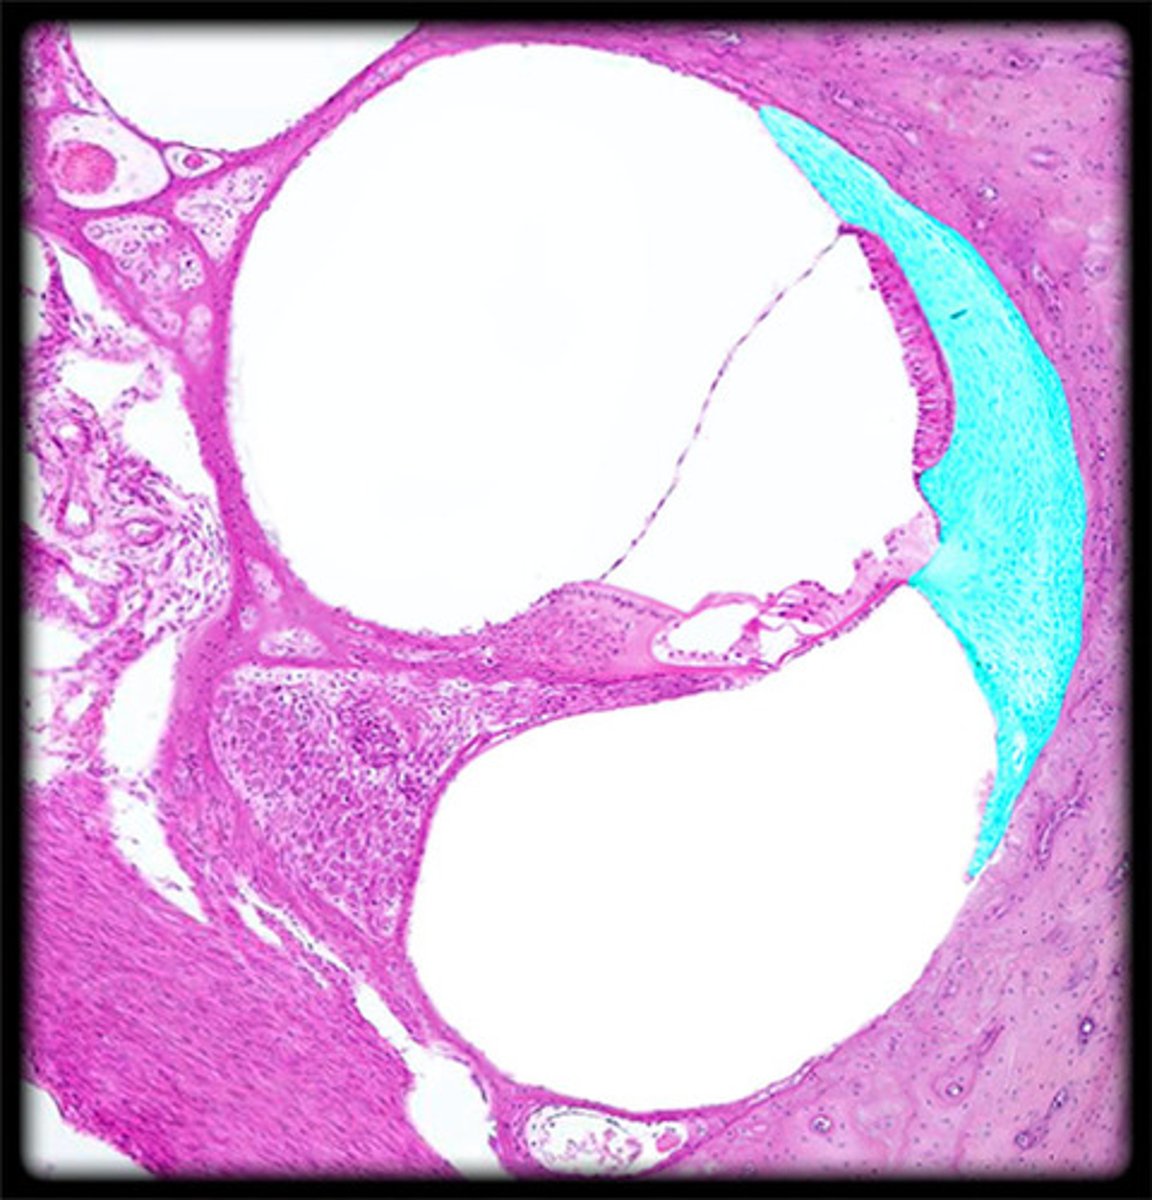

cochlea

a coiled, bony, fluid-filled tube in the inner ear through which sound waves trigger nerve impulses

scala vestibuli/vestibular duct

perilymph-filled top chamber of cochlea. Closest to vestibular system.

scala tympani

perilymph-filled cochlear chamber that connects to the round window

scala media

Middle chamber of the cochlea; filled with endolymph

perilymph

fluid that fills the bony labyrinth of the inner ear

endolymph

fluid within the membranous labyrinth of the inner ear

stria vascularis

external wall of cochlear duct composed of mucosa that secretes endolymph

Reissner's membrane (vestibular membrane)

membranous separation between scala vestibuli and scala media

spiral lamina

bony shelf that projects from the modiolus

spiral ligament

fibrous connective tissue on the lateral wall of the cochlear duct that supports the lateral edge of the basilar membrane

basilar membrane

runs the length of the cochlea in the inner ear and holds the hair cells.

organ of corti

Center part of the cochlea, containing hair cells, canals, and membranes

tectorial membrane

gelatinous, ribbon-like structure sitting atop the organ of corti